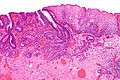

Micrograph showing histopathological appearance of an esophageal adenocarcinoma (dark blue – upper-left of image) and normal squamous epithelium (upper-right of image) at H&E staining